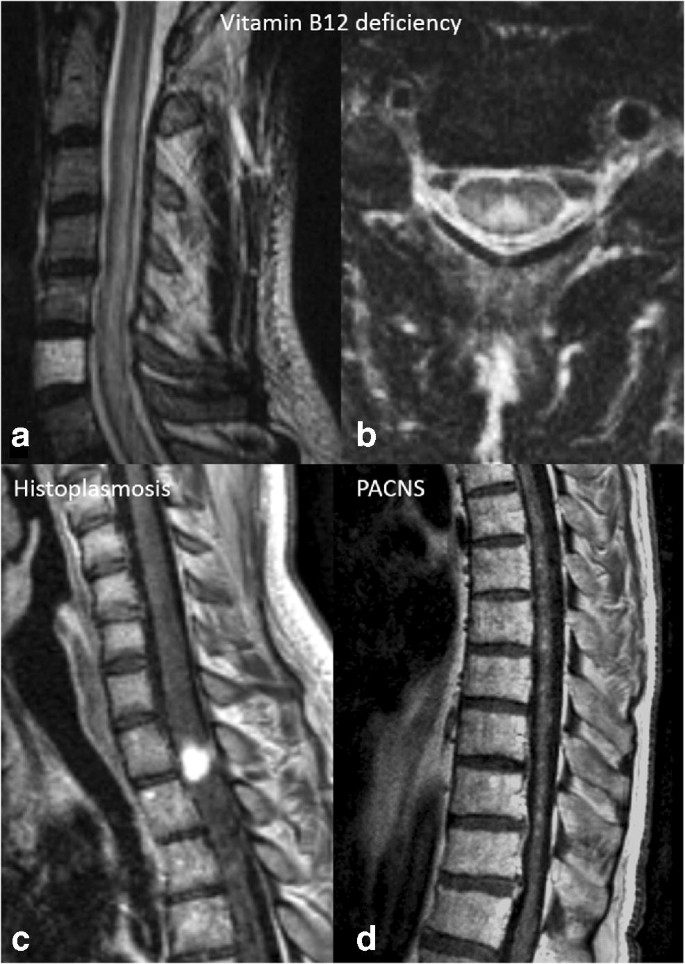

Subacute Combined Degeneration Of The Spinal Cord Due To Different Etiologies And Improvement Of Mri Findings

www.hindawi.com